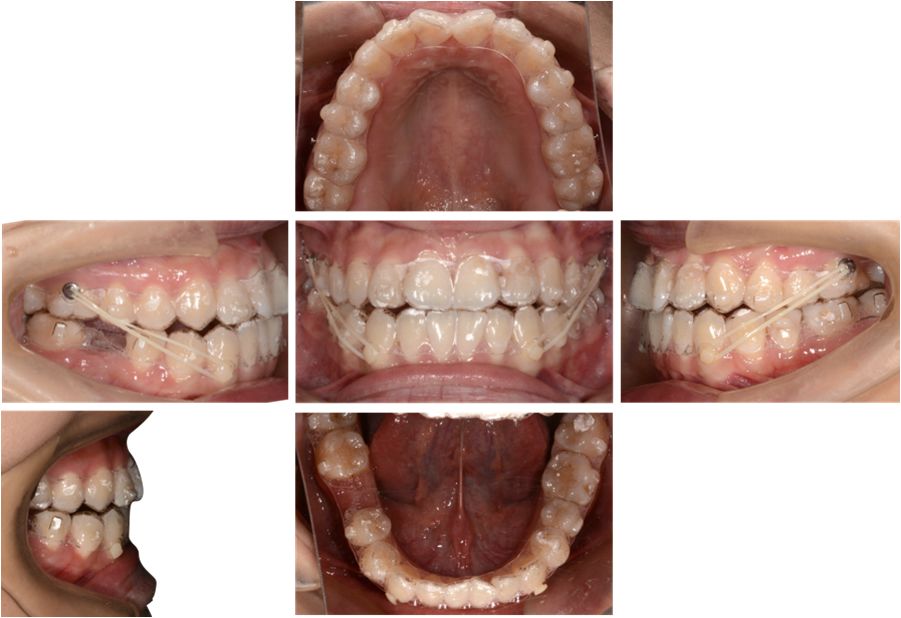

矫治中

第8副,矫治器与牙面贴合,矫治过程中配合III类牵引,有利于尖牙、磨牙关系的改善。

第20副,矫治器与牙面贴合,近中矩形附件使矫治器对47牙有较好的固位,47牙与45相对移动,磨牙尖牙关系改善。

第30副矫治器时,其余牙位矫治器还是比较贴合,但是47牙近中出现了低合与矫治器间隙变大,嘱患者使用咬胶,利用矫治器的力量竖直47牙。

第33副,由于47牙持续的前倾,我们进行了矫治设计的反馈,患者由于干扰的去除,咬合支点的前移,出现了颌位的后退。因为这个原因,实现了比矫治设计更好的尖牙磨牙关系。所以这次我们反馈时提交的是cr位的咬合记录。